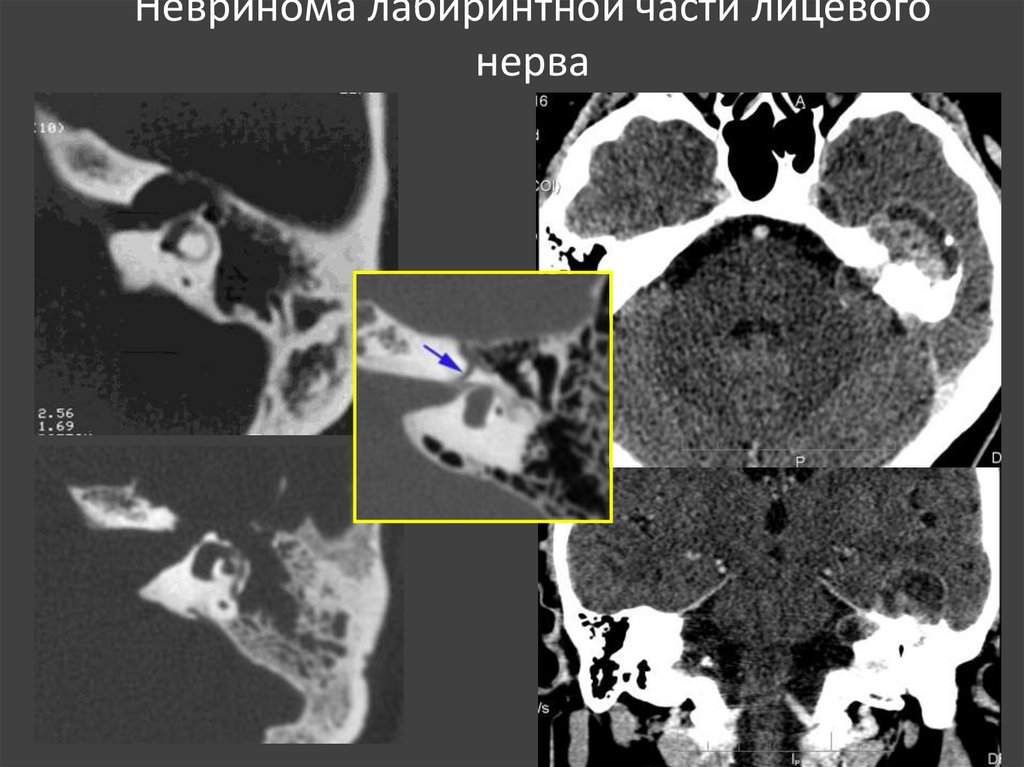

92. Невринома лабиринтной части лицевого нерва

93.